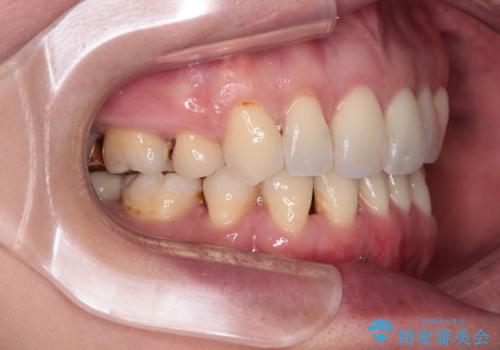

当初目論見通り、左右奥歯の咬み合わせはしっかりとさせることができました。

下唇に跡がつくほど飛び出していた上顎前歯も引っ込み、満足のいく仕上がりとなりました。